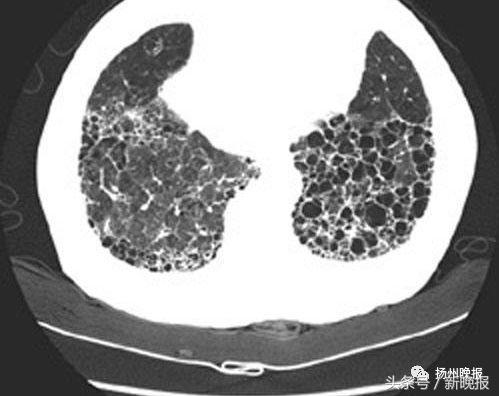

典型病例72岁健康爷爷患“蜂窝肺”手指头变得像肉球今年72岁的张爷爷是一体育爱好者平时有空还到处旅游虽已七旬,但连感冒都很少有可从去年底开始他感觉自己的身体有些不舒服“好好的干咳起来,上楼,出去买个菜,就气喘,晚上睡觉也感到呼吸不畅”。